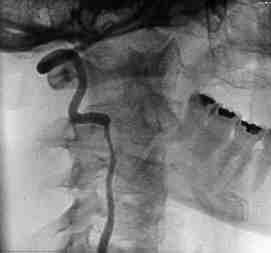

Fig 1. Arteriograf�a cerebral. Estenosis alargargada de la arteria vertebral (signo de la cuerda)

Fig 2. A. Vertebral cruza las 6 primeras vertebras cervicales para entrar al craneo por el agujero magno.